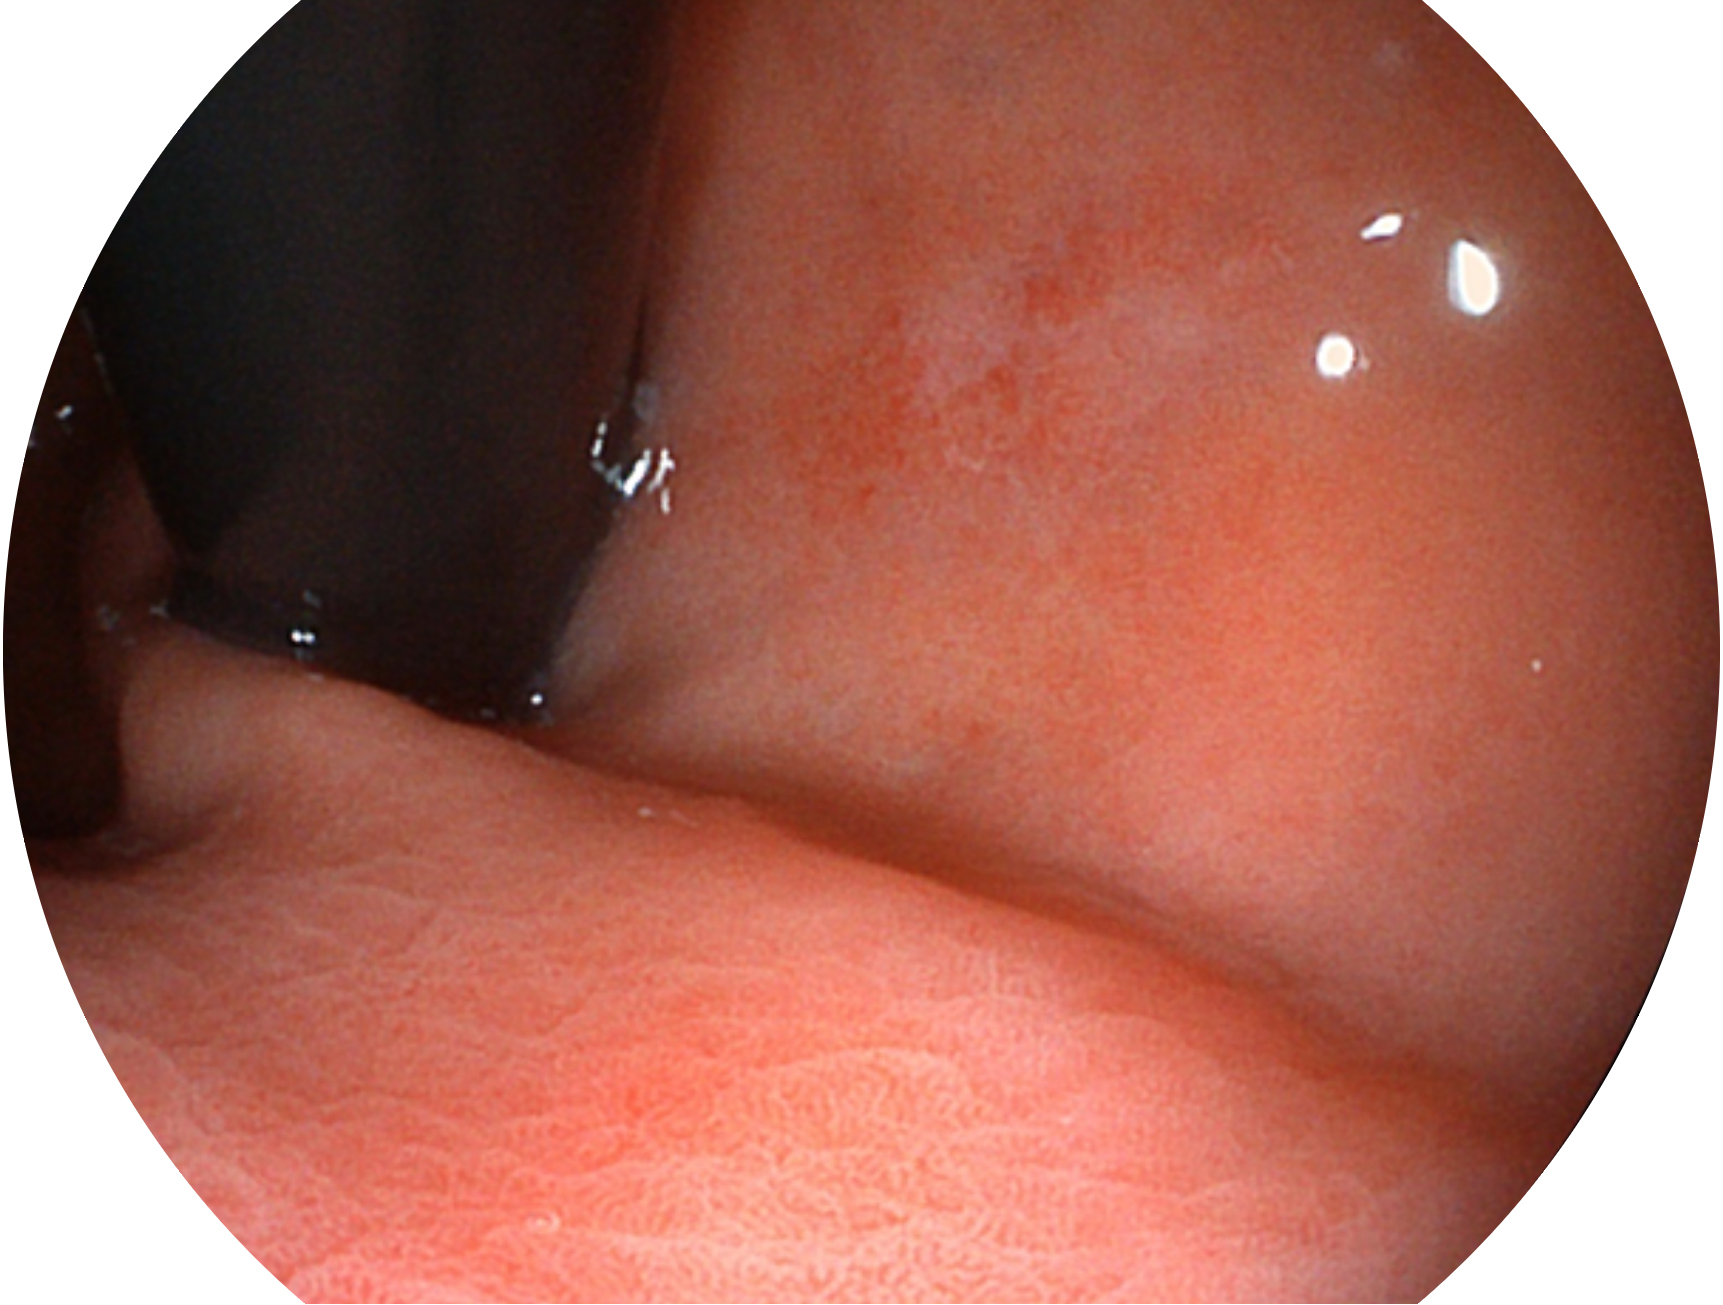

• 白光圖像 VIST圖像